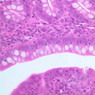

Examine slide B-4 (H&E [2.5x-labeled, 10x, 20x, 40x-labeled]) or B-5 (H&E [10x, 20x, 40x] [40x]) under the intermediate and high-dry objectives of your microscope. Mucous-secreting simple columnar cells, known as mucous surface cells, line the gastric lumen and the periodic deep depressions, known as gastric pits. The mucous surface cells differ from goblet cells both in their appearance and in the type of mucous they secrete. In H&E preparations they have a rather clear cytoplasm, but do not exhibit the sort of well-defined, unstained vacuoles that are typical of goblet cells. By contrast, in the PAS-stained section of slide B-6 (PAS [2.5x, 10x, 20x-labeled, 40x]) they stand out dramatically by virtue of their magenta-colored secretory product. As a rule, several glands extend from each gastric pit to the muscularis mucosae, largely obscuring the lamina propria. Small slips of smooth muscle that extend from the muscularis mucosae towards the luminal surface are presumed to be involved in expressing the glandular secretions.

As their name suggests, mucous neck cells are most numerous just proximal to the junction of gastric gland and gastric pit. In H&E-stained sections, these cells, like others which secrete mucous (e.g., goblet cells), tend to stain poorly on account of the loss of their secretory product during histological processing. However, in the section on slide B-6, which has been stained by the PAS technique, they are very easy to identify (bright pink). You should study the distribution of mucous neck cells in this slide and then attempt to identify them in H&E preparations by looking at corresponding regions in slide B-4 or B-5. What functions are served by the mucous-secreting cells of the gastric mucosa?